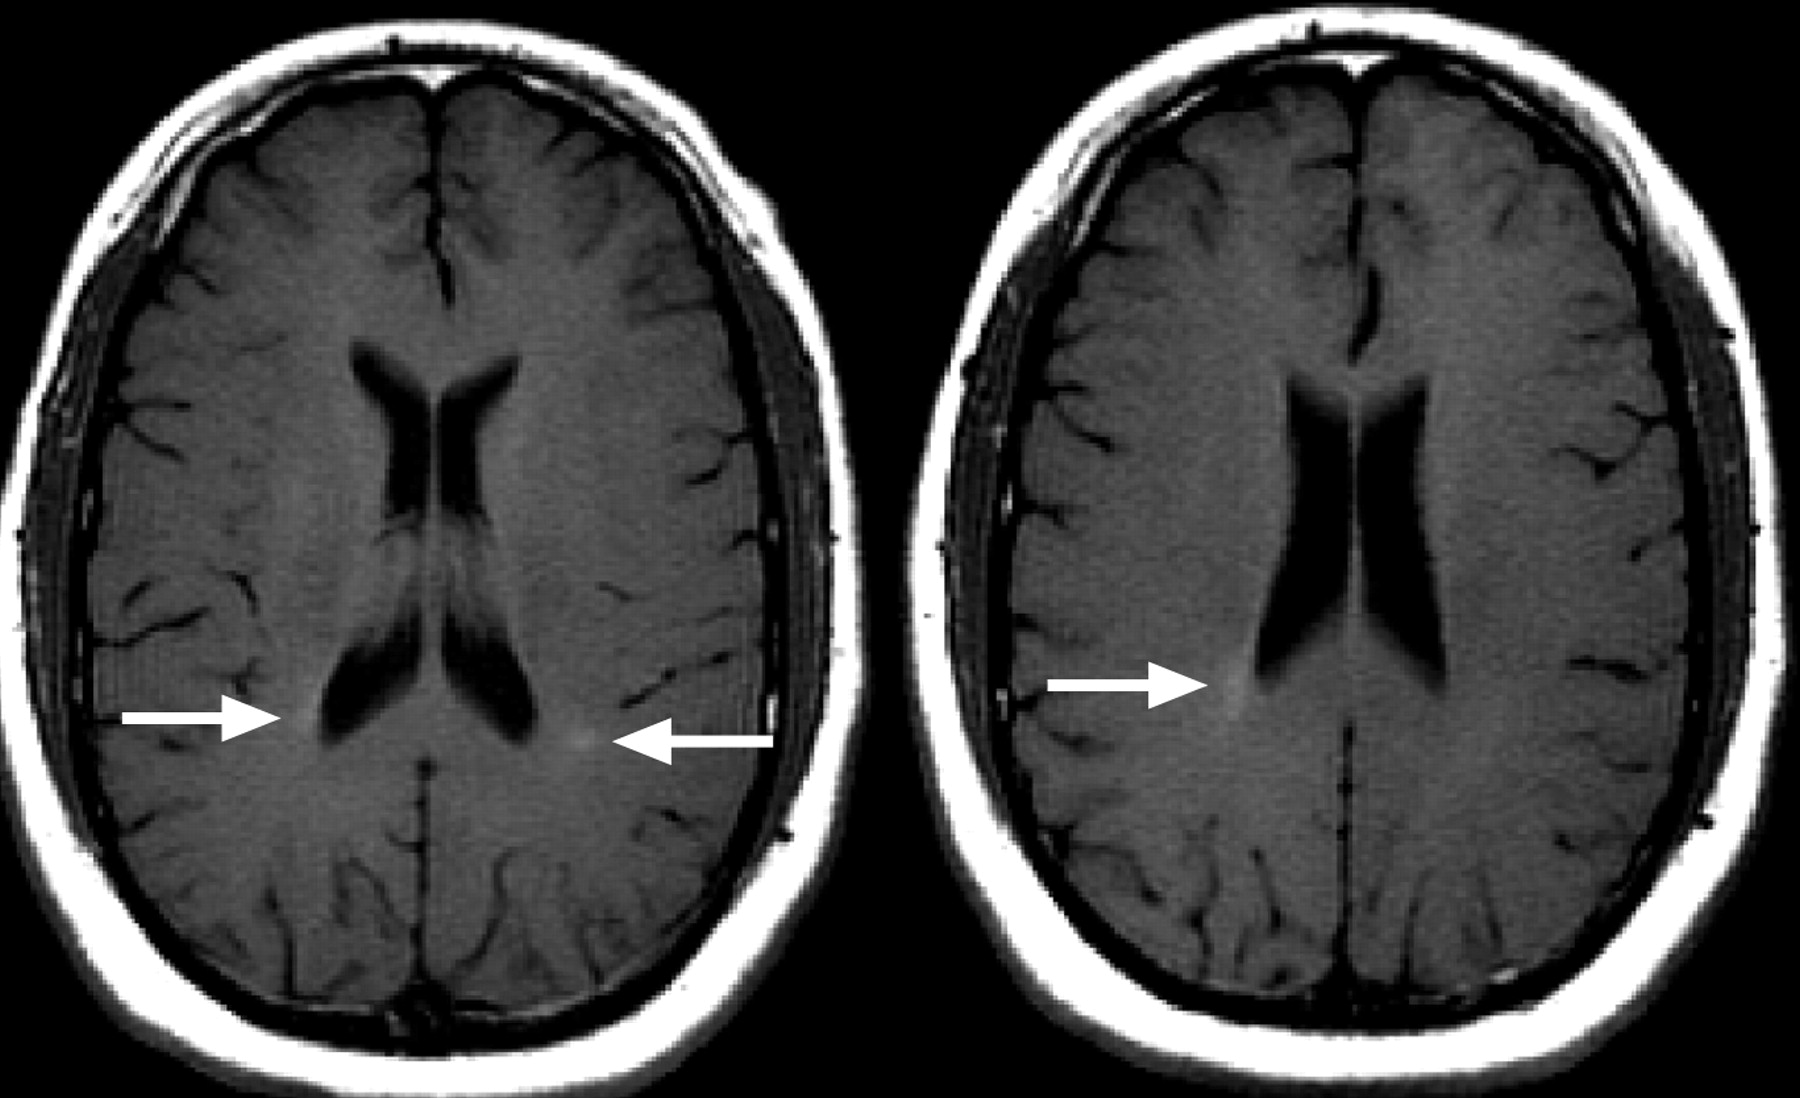

INTERVENTION: Each MSer had a brain MRI scan at entry and 6 months later using a standardized protocol.

MAIN OUTCOME MEASURES: The number of new T2 lesions, newly enlarging T2 lesions, and gadolinium-enhancing lesions were measured on the 6-month MRI using a computer-based image analysis program for the original study. For this study, images were reanalyzed by an expert neuroradiologist and 3 clinician raters. The neuroradiologist evaluated the original image pairs; the clinicians evaluated image pairs that were modified to simulate clinical practice. New lesion counts were compared across raters, as was classification of patients as MRI active or inactive.

RESULTS: Agreement on lesion counts was highest for gadolinium-enhancing lesions, intermediate for new T2 lesions, and poor for enlarging T2 lesions. In 18% to 25% of the cases, MRI activity was classified differently by the clinician raters compared with the neuroradiologist or computer program. Variability among the clinical raters for estimates of new T2 lesions was affected most strongly by the image modifications that simulated low image quality and different head position.

CONCLUSIONS: Between-rater variability in new T2 lesion counts may be reduced by improved standardization of image acquisitions, but this approach may not be practical in most clinical environments. Ultimately, more reliable, robust, and accessible image analysis methods are needed for accurate multiple sclerosis disease-modifying drug monitoring and decision making in the routine clinic setting.